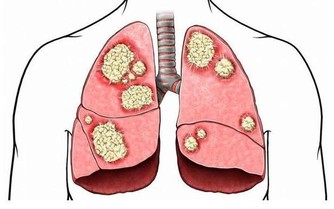

肺癌是“癌症之王”,是人類死亡的頭號殺手。肺癌的發病率男性多於女性,城市多於農村。

肺癌並非吸煙一族的專利,經常接觸二手煙、做飯的女性也是肺癌的高危人群。肺癌的致病因素比較複雜,空氣污染、環境因素、粉塵、刺激性氣味環境、遺傳史等等都是導致肺癌的致命因素,它就像一種慢性病一樣,在某種致病因素的長期刺激下,正常細胞會發生癌變,慢慢地形成腫瘤。據了解,閆懷禮在河北涿州拍攝一部叫《俏羅城》的電視劇。當地的蒼蠅、蚊子特別多,當時有一場戲拍戲的現場噴灑了很多敵敵畏,很多人都因為濃重的味道離開了,當時閆懷禮嗅覺不好感覺不到,長時間處在敵敵畏濃重的環境裡面,拍戲空擋還在那裡休息,好友六小齡童分析這是他患病的誘因之一,再加上多年拍戲工作太過勞累,閆懷禮才患上了肺癌。

1、小細胞肺癌:癌細胞生長快,轉移快

據肺癌幫APP病例庫統計,小細胞肺癌約佔10%。小細胞肺癌,其癌細胞生長的速度快,轉移也迅速,且容易有抗藥性,大多為吸煙所引起,也與環境或基因有關。

2、肺腺癌:最常見,多為女性

肺腺癌約佔50%,以女性為主。肺腺癌為最常見的肺癌,也是不吸煙者(多數為女性的45歲以下)常見的類型,容易遠端轉移是其特徵。治療的原則得根據期別,通常一、二期可經由評估後進行手術,之後再做化療等。

3、鱗狀上皮細胞癌:早期多為局部向外延伸的轉移

鱗狀上皮細胞癌,約佔30%,吸煙男士居多。常常發生在男性吸煙者,早期多為局部向外延伸的轉移,後期則經由血路擴散。

4、大細胞肺癌:生長速度快,預後不佳

患者人數約佔肺癌的5%,生長速度較快,會迅速經由血路及淋巴擴散,預後不佳。